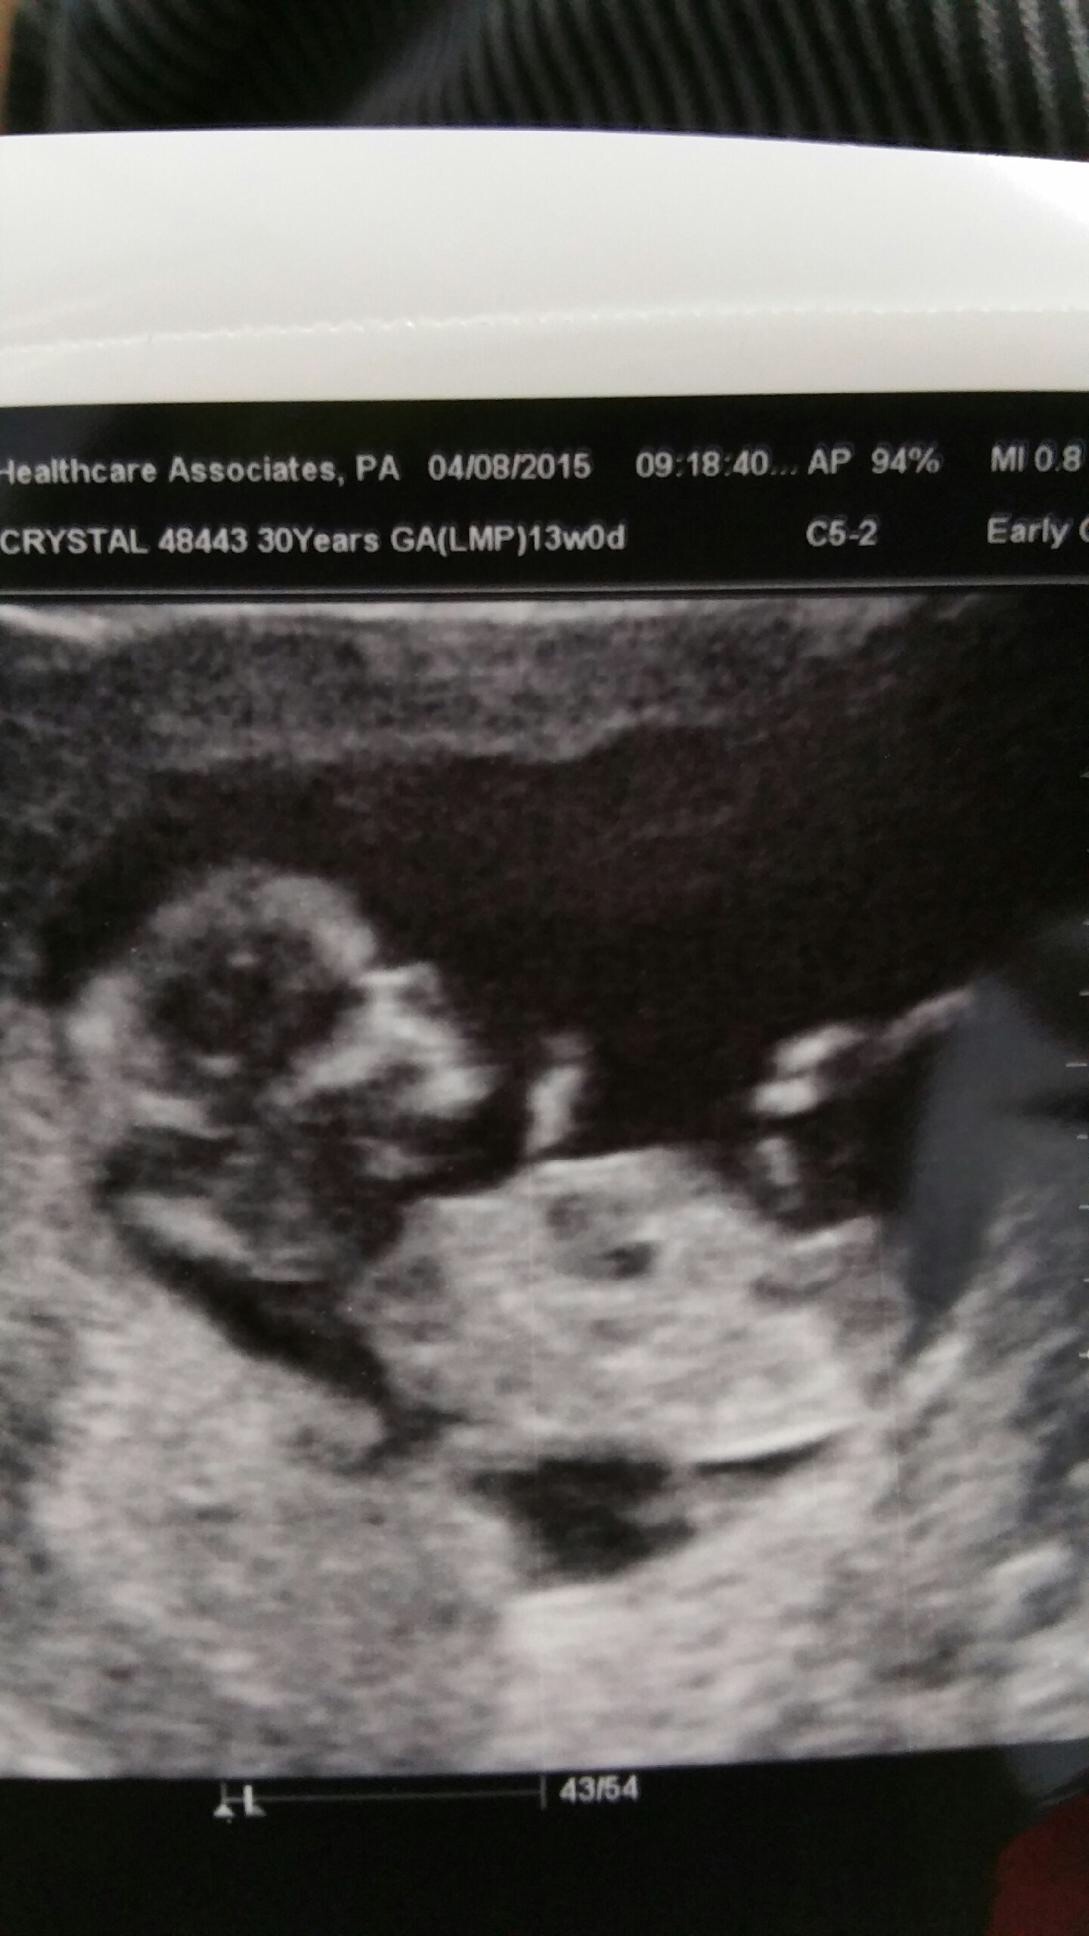

14 weeks, 1 day. I had an abdominal u/s. I've decided to call it my little wiggle worm because it wouldn't stop moving around, and stretching! It took three tries for the tech to capture the heartbeat (148). At one point she managed to get positioned just right to see it's entire front, and not even a second later, it completely turned itself around

Got a surprise ultrasound today at 14w1d- thought we were just going to hear the heartbeat but we got pics too! Last time was at 9 weeks and she looked like a white smear on the U/S. Now look! So exciting!!